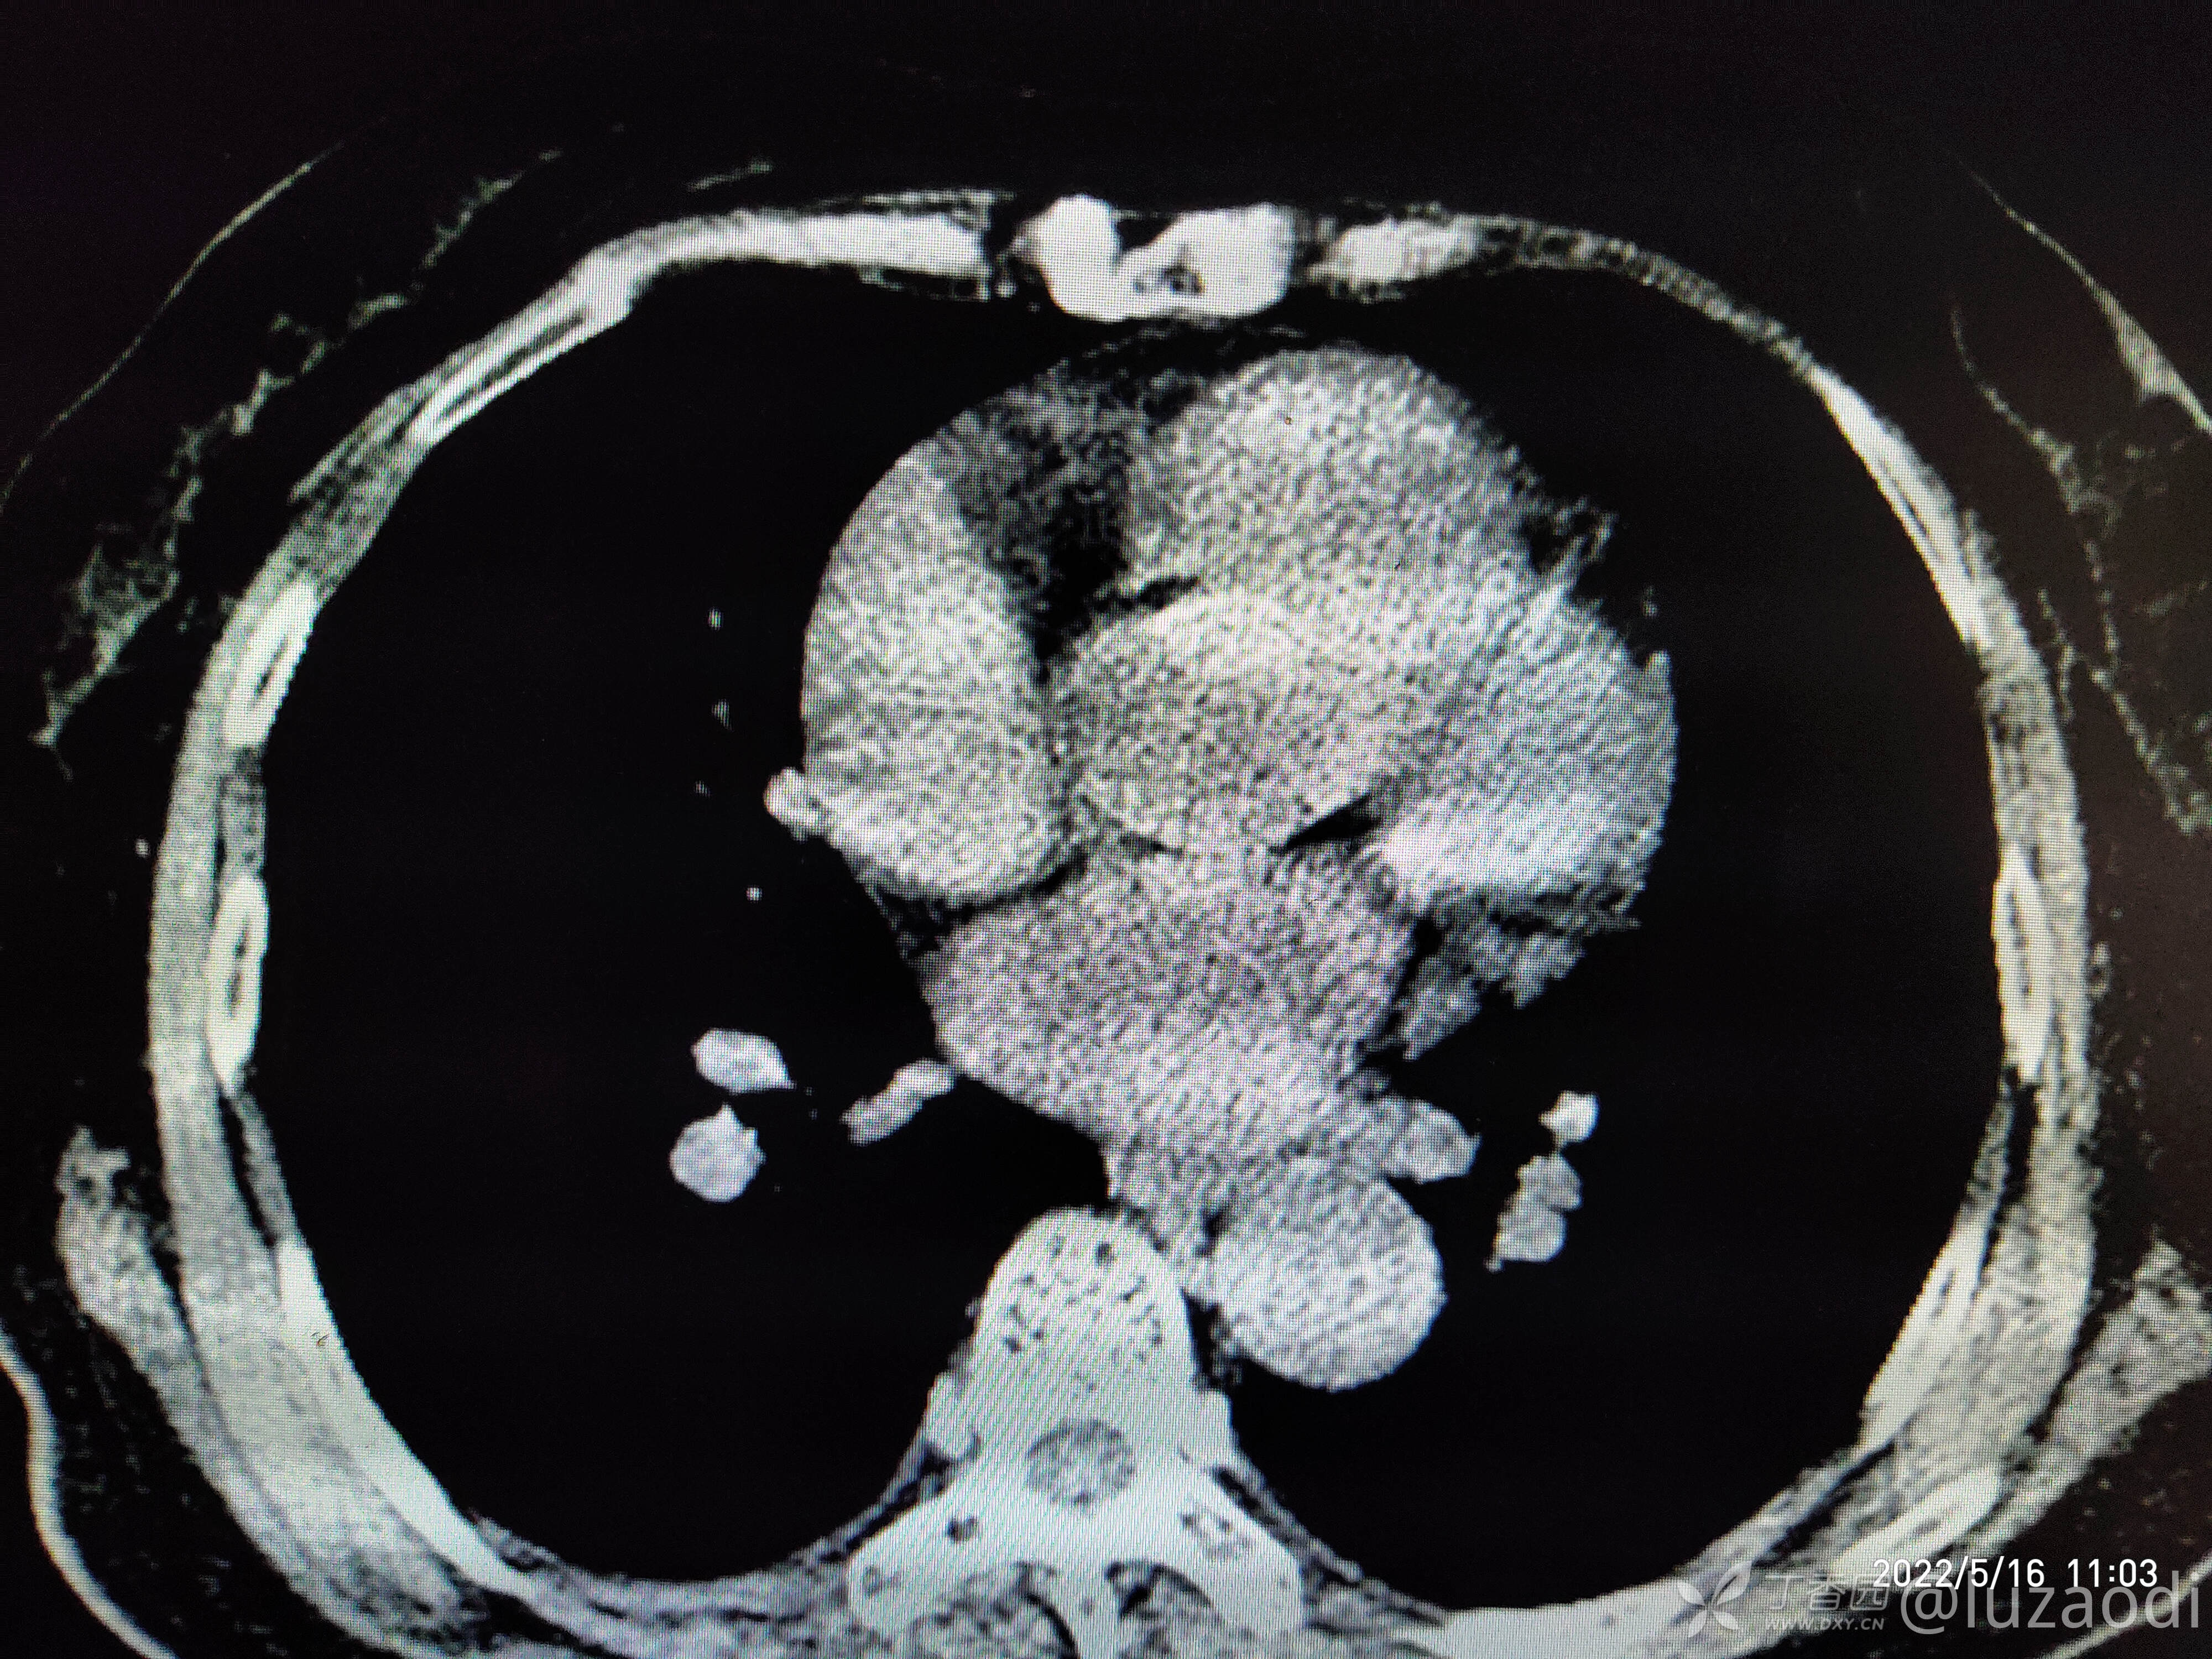

治疗经过:入院后患者仅有乏力,未见明显神经定位征。近期无发热、咳嗽、腹泻症状。遂予血糖、心电图、生化检查及影像检查,结果如下:

心电图将就着看,因为是手机拍的。

我去。。。。。视频只能上传一个,头颅CT上传不了,我直接说报告吧。头颅CT报腔隙性脑梗。